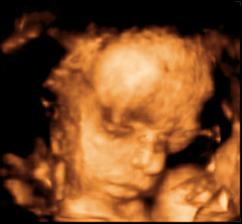

26 tt../1.4.2009/ naša paulínka je stráášne zlatá, boli sme si pozrieť na 4D utz. ..tvárila sa veľmi dôležito, až nafúkano...hehe..vôbec sa nechcela usmievať... nakoniec sa nám aj zasmiala...v brušku veľmi vyvádza, maminke dosť vytláča všetky časti telíčka, čo je niekedy aj dosť bolestivé...ale vydržíme, drobečkovi je tam určite tiež pritesno..a ešte aj stále viac a viac bude... strááášne sa na ňu tešíme🙂))